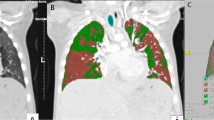

All examinations were analyzed in a commercially available workstation (Advantage Workstation 4.6, General Electric Healthcare Technologies, Waukesha, WI, USA). Inspiratory and expiratory CT images were evaluated using dedicated software designed for the assessment of segmented images from the chest wall, mediastinum, diaphragm, and airways. Automated segmentation of the transplanted lung from the chest wall and mediastinum was performed and the total lung volume and attenuation of all voxels included in the lung segmentation were quantified. The expiratory air-trapping index (ATIexp) was calculated as the percentage of lung voxels with attenuation of − 950 to − 856HU on expiratory CT images [15] (Fig. 1). Mean lung density (MLD) histograms were created for expiratory and inspiratory acquisitions for each subject, and the expiration and inspiration ratio of MLD (E/I-ratio(MLD) was calculated [22, 23]. Measurements were performed by 2 thoracic radiologists in consensus, with a minimum of 10 years of experience, blinded to all clinical information. Analysis of all measurements required approximately five minutes per patient.

Coronal (1A) and axial (1B) slices of expiratory high resolution CT scan of the chest from a single lung transplant patient with BOS. Images 2A, 2B e 2C show the 3D-CT reconstruction of the lungs and images 3A, 3B e 3C show the same 3D-CT reconstruction highlighting areas of air trapping in the transplanted lung only (red color), represented by lung voxels with attenuation of − 950 to − 856 HU